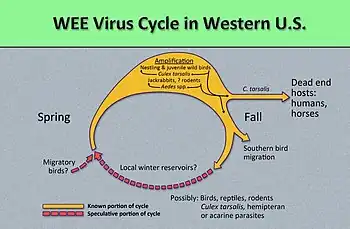

| This diagram illustrates the methods by which the arbovirus, Western equine encephalitis virus (WEEV) reproduces and amplifies itself in both avian populations, and rodent populations, and is subsequently transmitted to dead end hosts including humans and horses by the Culex tarsalis mosquito. Western equine encephalitis virus, is a member of the family Togaviridae, and the genus Alphavirus, is closely related to Eastern and Venezuelan equine encephalitis viruses. | |